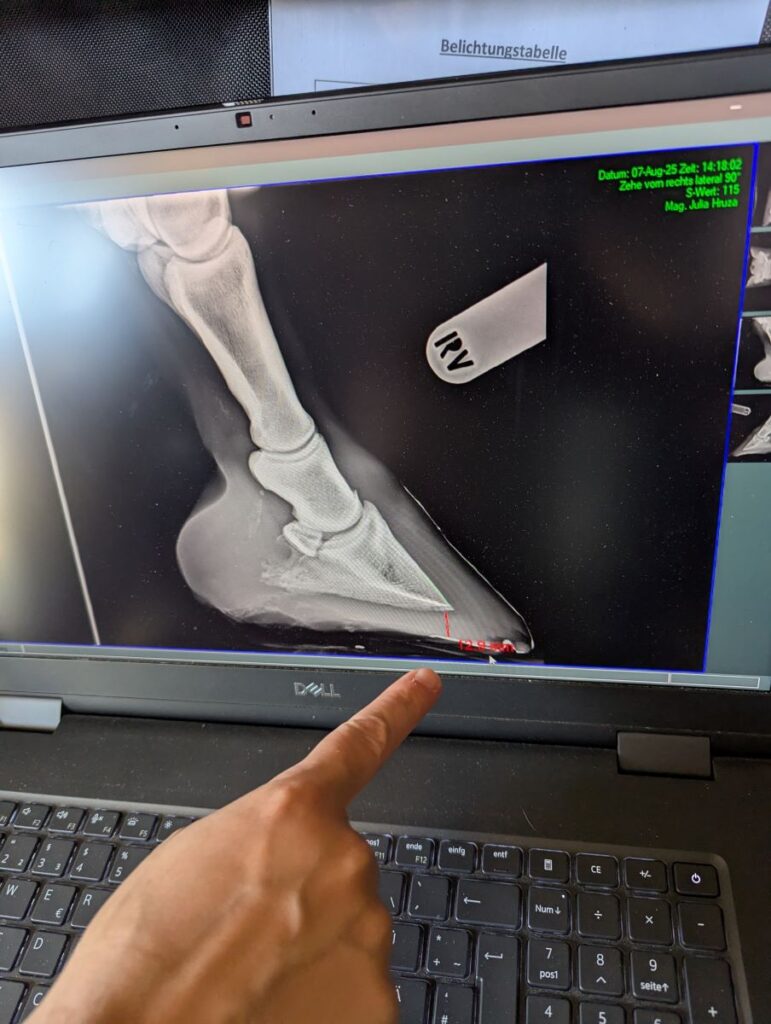

Das heißt aber nicht, dass du dich selber nicht auch mit den Bildern beschäftigen kannst (oder eigentlich solltest). Die Diagnose muss auf jeden Fall von deiner/m Tierärzt*in kommen, aber damit du selber auch verstehen kannst, was auf den Röntgen deines Pferdes zu sehen ist, haben wir hier einen etwas nerdigen Beitrag zur Interpretation der Sohlendicke bei Hufröntgen erstellt: Sohlendicke auf Huf-Röntgenbildern korrekt bestimmen. Viel Spaß beim Weiterlesen!

Ohne die passenden Bilder wäre dieser Beitrag nur halb so anschaulich. Vielen Dank an Mag.a Julia Hruza (pferdepraxis-hruza.at) für die freundliche Genehmigung, ihre Aufnahmen hier verwenden zu dürfen!